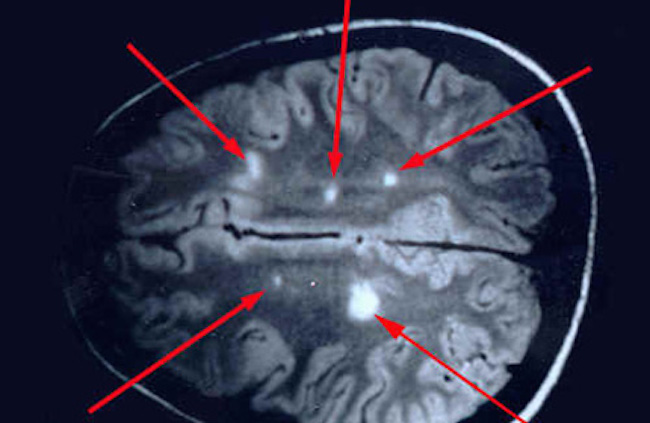

Medical research shows that the living Borrelia bacteria were found in the brains of people who had been diagnosed with MS.

Theeventchronicle.com reports: Time and time again. By at least a dozen medical researchers. In at least ten countries. Since 1911 – the past one hundred years. Several older but also recent autopsy findings linked to in this article found that all deceased MS patients’ brains harbored living Lyme spirochetes. Even when tests, notorious for their large percentage of false negatives were used on living MS patients, staggeringly many tested positive for active Lyme borreliosis.